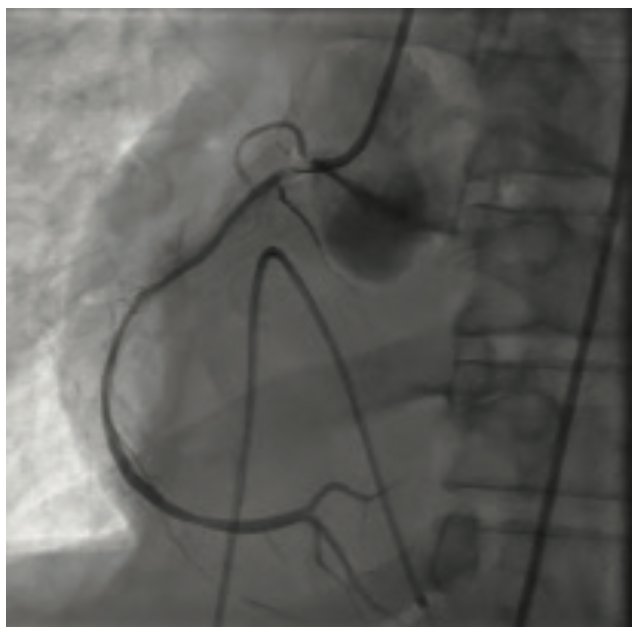

He clinically improved and on the second hospital day, underwent diagnostic cardiac catheterization. He did not have palpable radial pulses bilaterally; therefore, a femoral approach was used. His right external iliac artery and right common femoral artery were occluded. His distal aorta was heavily calcified with a high-grade eccentric stenosis. He also had a proximal 70%-80% left common iliac artery stenosis. Diagnostic coronary angiographic findings demonstrated a heavily calcified ostial 99% lesion in the right coronary artery (RCA) with significant calcium accumulation throughout the mid RCA. The left main coronary artery appeared heavily calcified, with a wedge-shaped filling defect suggesting a high-grade eccentric stenosis. The proximal left anterior descending (LAD) artery was very tortuous with a heavily calcified lesion at the first diagonal that extended into the ostium of the diagonal vessel. The circumflex artery was totally occluded. The patient’s ejection fraction based on ventriculography was 35% to 40%, with the posterior lateral wall being akinetic. He was extubated following the cardiac catheterization. Cardiothoracic surgery was consulted to provide an opinion regarding surgical revascularization. Due to his multiple comorbidities, he was felt to be high risk and not a surgical candidate. A plan for percutaneous revascularization was discussed with the patient. The nature and purpose of the procedure along with expected outcomes, together with the reasonably known risks were explained. He acknowledged that such disclosure of information had been made and that all questions asked about the procedure had been answered. He demonstrated understanding and legal capacity to consent and therefore, the written consent was obtained by his signature. The intervention was performed on hospital day 5. The patient was discharged home on hospital day 7.

The RCA was initially treated with orbital atherectomy. The 1.25 mm x 145 cm Diamondback 360˚ orbital atherectomy system (CSI) was advanced over the wire. Multiple passes at low speed were performed to reduce the ostial RCA lesion. Treatment was performed from proximal to distal, with the tip of the catheter crown just within the ostium prior to spinning. After multiple passes, luminal gain was observed angiographically in the ostial portion of the vessel. The crown was then traversed on low speed through the mid RCA just proximal to the distal portion of the vessel. Balloon angioplasty was performed prior to deploying two drug-eluting stents to cover the orbital atherectomy treatment zone from the distal RCA retrograde to cover the RCA ostium. No slow flow or dissections were noted angiographically and the patient remained hemodynamically stable throughout the RCA intervention. A Xience Skypoint 2.75 mm x 33 mm stent (Abbott Vascular) was advanced into the distal RCA and deployed at 12 atmospheres (atm). This was followed by a 3.0 mm x 33 mm Xience Skypoint stent, deployed in the mid RCA, and finally, a 3.5 mm x 28 mm Xience Skypoint stent was deployed proximally. The stents were post dilated with a 3.0 mm x 20 mm, 3.5 mm x 20 mm, and 4.0 mm x 20 mm NC Trex RX balloon (Abbott Vascular) at 20 atm. Completion angiography was performed. We chose to proceed to treating the left coronary tree.

The left main artery was cannulated with a 6 Fr XBLAD 3.5 guiding catheter (Cordis). The Whisper wire was used to cross the stenosis. IVUS was performed using an .014 Eagle Eye Platinum ultrasound catheter (Philips Volcano). In the same fashion as the RCA, the Whisper wire was exchanged for the ViperWire. The LM was subsequently treated with orbital atherectomy. Multiple passes were performed in opposition to the 70% nodular, calcified lesion that was fully identified on IVUS imaging. Once luminal gain was identified angiographically in the LM, the atherectomy crown was traversed distally into the calcified lesion in the proximal LAD. After two passes in the proximal LAD, the crown was traversed into the mid LAD lesion at the level of the first diagonal branch. Orbital atherectomy was again performed, reducing the calcium burden in both the LAD and the ostium of the diagonal branch. Balloon angioplasty was performed from mid LAD retrograde to the LM using a 3.0 mm x 20 mm NC Trek balloon. Following the balloon angioplasty, drug-eluting stents (3.0 mm x 15 mm Xience Skypoint, 3.5 mm x 38 mm Xience Skypoint, and a 5.0 mm x 30 mm Resolute Onyx drug-eluting stent [Medtronic], placed distal to proximal) were deployed from the mid LAD proximally to the LM, covering the orbital atherectomy-treated zone. The patient remained hemodynamically stable throughout the procedure. A completion angiogram was obtained. No slow flow or dissections were noted.